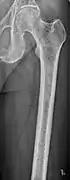

X-ray of the forearm, with lytic lesions

Multiple myeloma in the upper arm

Femur with multiple myeloma lesions

Humerus with multiple myeloma lesions

The diagnostic examination of a person with suspected multiple myeloma typically includes a skeletal survey. This is a series of X-rays of the skull, axial skeleton, and proximal long bones. Myeloma activity sometimes appears as "lytic lesions" (with local disappearance of normal bone due to resorption) or as "punched-out lesions" on the skull X-ray ("raindrop skull"). Lesions may also be sclerotic, which is seen as radiodense.[70] Overall, the radiodensity of myeloma is between −30 and 120 Hounsfield units (HU).[71] Magnetic resonance imaging is more sensitive than simple X-rays in the detection of lytic lesions, and may supersede a skeletal survey, especially when vertebral disease is suspected. Occasionally, a CT scan is performed to measure the size of soft-tissue plasmacytomas. Nuclear Medicine Bone scans are typically not of any additional value in the workup of people with myeloma (no new bone formation; lytic lesions not well visualized on nuclear bone scan).